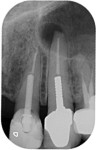

Molar retreatment